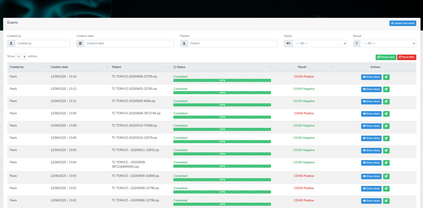

COVID-19 infection caused by SARS-CoV-2 pathogen is a catastrophic pandemic outbreak all over the world with exponential increasing of confirmed cases and, unfortunately, deaths. In this work we propose an AI-powered pipeline, based on the deep-learning paradigm, for automated COVID-19 detection and lesion categorization from CT scans. We first propose a new segmentation module aimed at identifying automatically lung parenchyma and lobes. Next, we combined such segmentation network with classification networks for COVID-19 identification and lesion categorization. We compare the obtained classification results with those obtained by three expert radiologists on a dataset consisting of 162 CT scans. Results showed a sensitivity of 90\% and a specificity of 93.5% for COVID-19 detection, outperforming those yielded by the expert radiologists, and an average lesion categorization accuracy of over 84%. Results also show that a significant role is played by prior lung and lobe segmentation that allowed us to enhance performance by over 20 percent points. The interpretation of the trained AI models, moreover, reveals that the most significant areas for supporting the decision on COVID-19 identification are consistent with the lesions clinically associated to the virus, i.e., crazy paving, consolidation and ground glass. This means that the artificial models are able to discriminate a positive patient from a negative one (both controls and patients with interstitial pneumonia tested negative to COVID) by evaluating the presence of those lesions into CT scans. Finally, the AI models are integrated into a user-friendly GUI to support AI explainability for radiologists, which is publicly available at http://perceivelab.com/covid-ai.